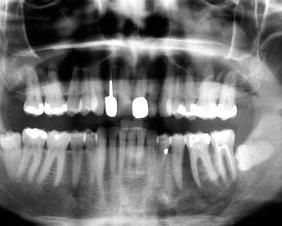

根據病史、臨床表現和局部檢查,配合X線片即可確定診斷。中央性骨髓炎的X線片早期無變化,2-4周后可見骨質疏鬆密度減低區,2-3個月後,顯示骨破壞局限有死骨形成或病理性骨折。